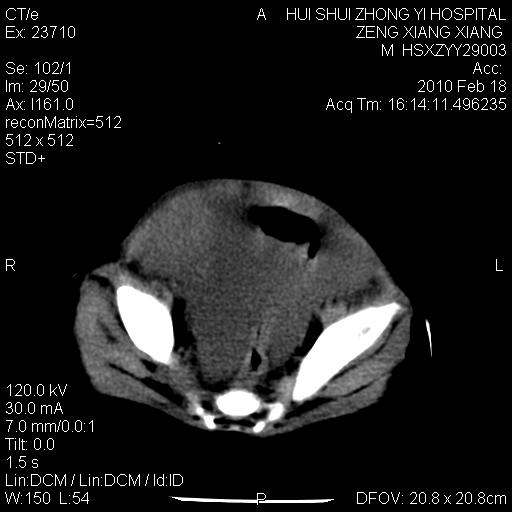

标题: PED3106:男,2岁,腹胀1月。 [打印本页]

标题: PED3106:男,2岁,腹胀1月。

定位腹膜后,肾上腺来源;

定性:恶性神经源性,肾上腺神经节母细胞瘤可能性大。

鉴别:肝母、肾母、肝脏中胚层错构瘤。

依据:年龄、有钙化,肾脏及肝脏受压移位。

肝母细胞瘤可能性大,右肾形态大体可见,不支持肾母细胞瘤,右肾移位不明显,肾上腺神经母细胞瘤可能性不大。